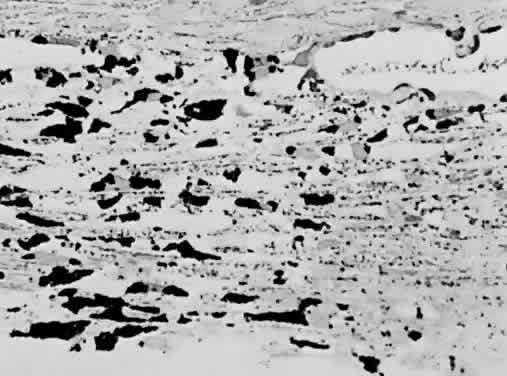

Accumulation of exfoliative material may be detected histopathologically throughout the anterior segment to include the lens, iris, trabecular structures, conjunctiva, ciliary body, and zonules. The deposition of fibrillar eosinophilic material on the anterior lens capsule is the classic histopathologic feature of XFS (Fig. 9). Ultrastructural studies also indicate some degree of actual exfoliative changes or peeling of the anterior lens capsule74 (Figs. 10 and 11). In addition, Ashton and associates describe a degenerative band containing exfoliative material within the inner half of the lens capsule.5 Bertelsen and coworkers independently noted projection of coarse fibrils from the lens surface into the deep portion of the lens capsule to form an amorphous layer of the lens capsule between the lens epithelium and normal lens capsule.6 Thus, studies indicate that exfoliative material accumulates on the anterior lens surface but also that the lens capsule itself may be involved, and that the underlying epithelial layer may at least partially contribute to the production of the exfoliative material.

Exfoliative material consists of an irregular meshwork of fibers composed of fibrillar subunits.74,92 Masses of these fibers correspond to the material seen clinically (see Fig. 10). The individual fibrils, which measure 6 to 8 nm in diameter and exhibit cross-banding at 10- to 12-nm intervals, are hypothesized to consist of macromolecules with a protein backbone and polysaccharide side chains.93–95 In contrast to collagen, the amino acid content of exfoliative material lacks hydroxyproline.96 Ringvold and Husby noted histochemical, immunologic, and ultrastructural features that led them to classify exfoliative material as an amyloid-like substance.97 Repo and associates note Congo red-positive staining for amyloid in the vessel walls of 7 of 13 iris specimens from exfoliation patients and believe that these findings support the theory that XFS is associated with amyloid.59 Immunohistochemical studies by other investigators show heparin sulfate and chondroitin sulfate proteoglycans, laminin, entactin/nidogen, fibronectin, and amyloid P protein to be components of exfoliation material.98,99 Schlötzer-Schrehardt and coworkers suggest that the material may be an expression of a disordered extracellular matrix synthesis.98